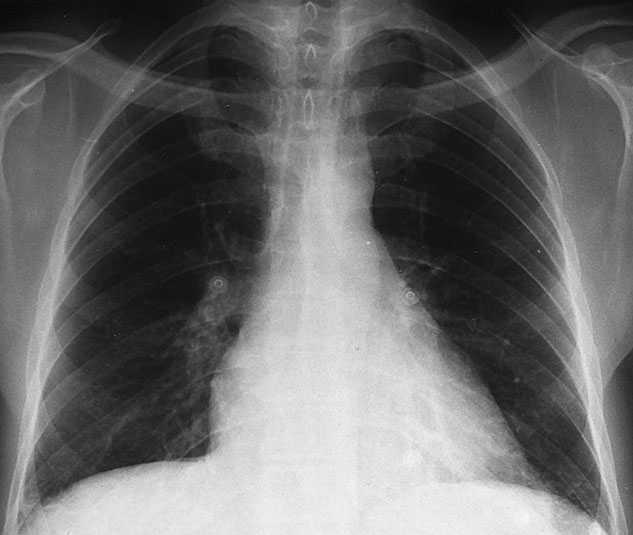

La radiografía de tórax demuestra engrosamiento pleural bilateral, paquipleuritis calcificada en el lado izquierdo, retracción biliar y granulomas en LSI con patrón fibroso retráctil.